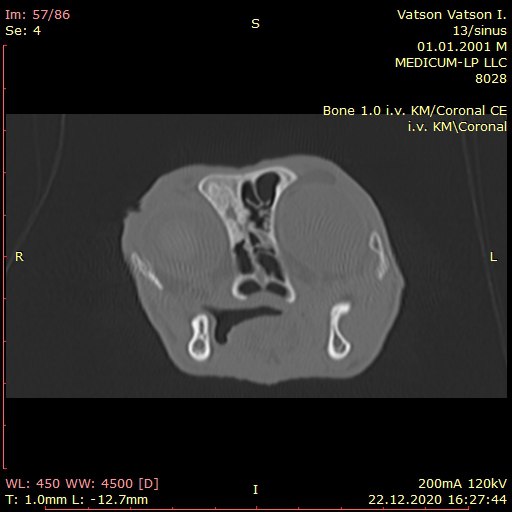

🔴Це безболісна і безпечна процедура для тварини. Проводиться з використанням седативних засобів. Оскільки найменших рух тварини може перешкодити отриманню якісного знімку.

🩺Тому перед процедурою необхідно зробити аналізи крові та кардіо УЗД.

Протипоказання:

📍 Вагітність

📍 Непереносимість седативних засобів